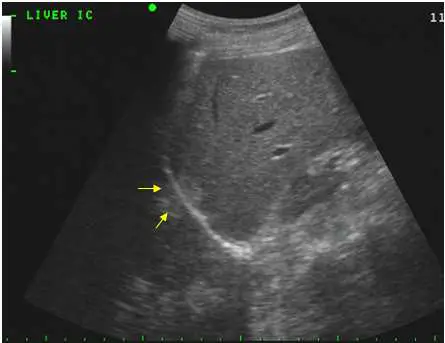

圖中標示為「LIVER IC」(肝臟肋間掃描),可見:

- 肝臟實質位於影像上半部,呈均勻中等回聲

- 兩支黃色箭號指向橫膈膜的強回聲弧形線(高亮弧帶),以及橫膈膜**深方(後方)**出現的一段肝臟實質複製影像

- 橫膈膜後方的影像應為充氣肺臟,正常不應出現實質回聲;此處出現的「肝臟幻影」正是鏡像假影的典型表現

- 兩張影像(真實肝臟與鏡像肝臟)對稱分布於橫膈膜兩側,符合鏡像假影定義

(A) 鏡像假影 ✔ 超音波束從肝臟向下傳遞,撞擊高反射性的橫膈膜—肺臟介面後,被反射回肝臟,再由肝臟內部結構反射至橫膈膜,最終回到探頭。由於儀器假設聲波走直線,會將這段「多次反射」的回波定位在比橫膈膜更深處,形成肝臟的鏡像。圖中箭號正指向此鏡像影像。